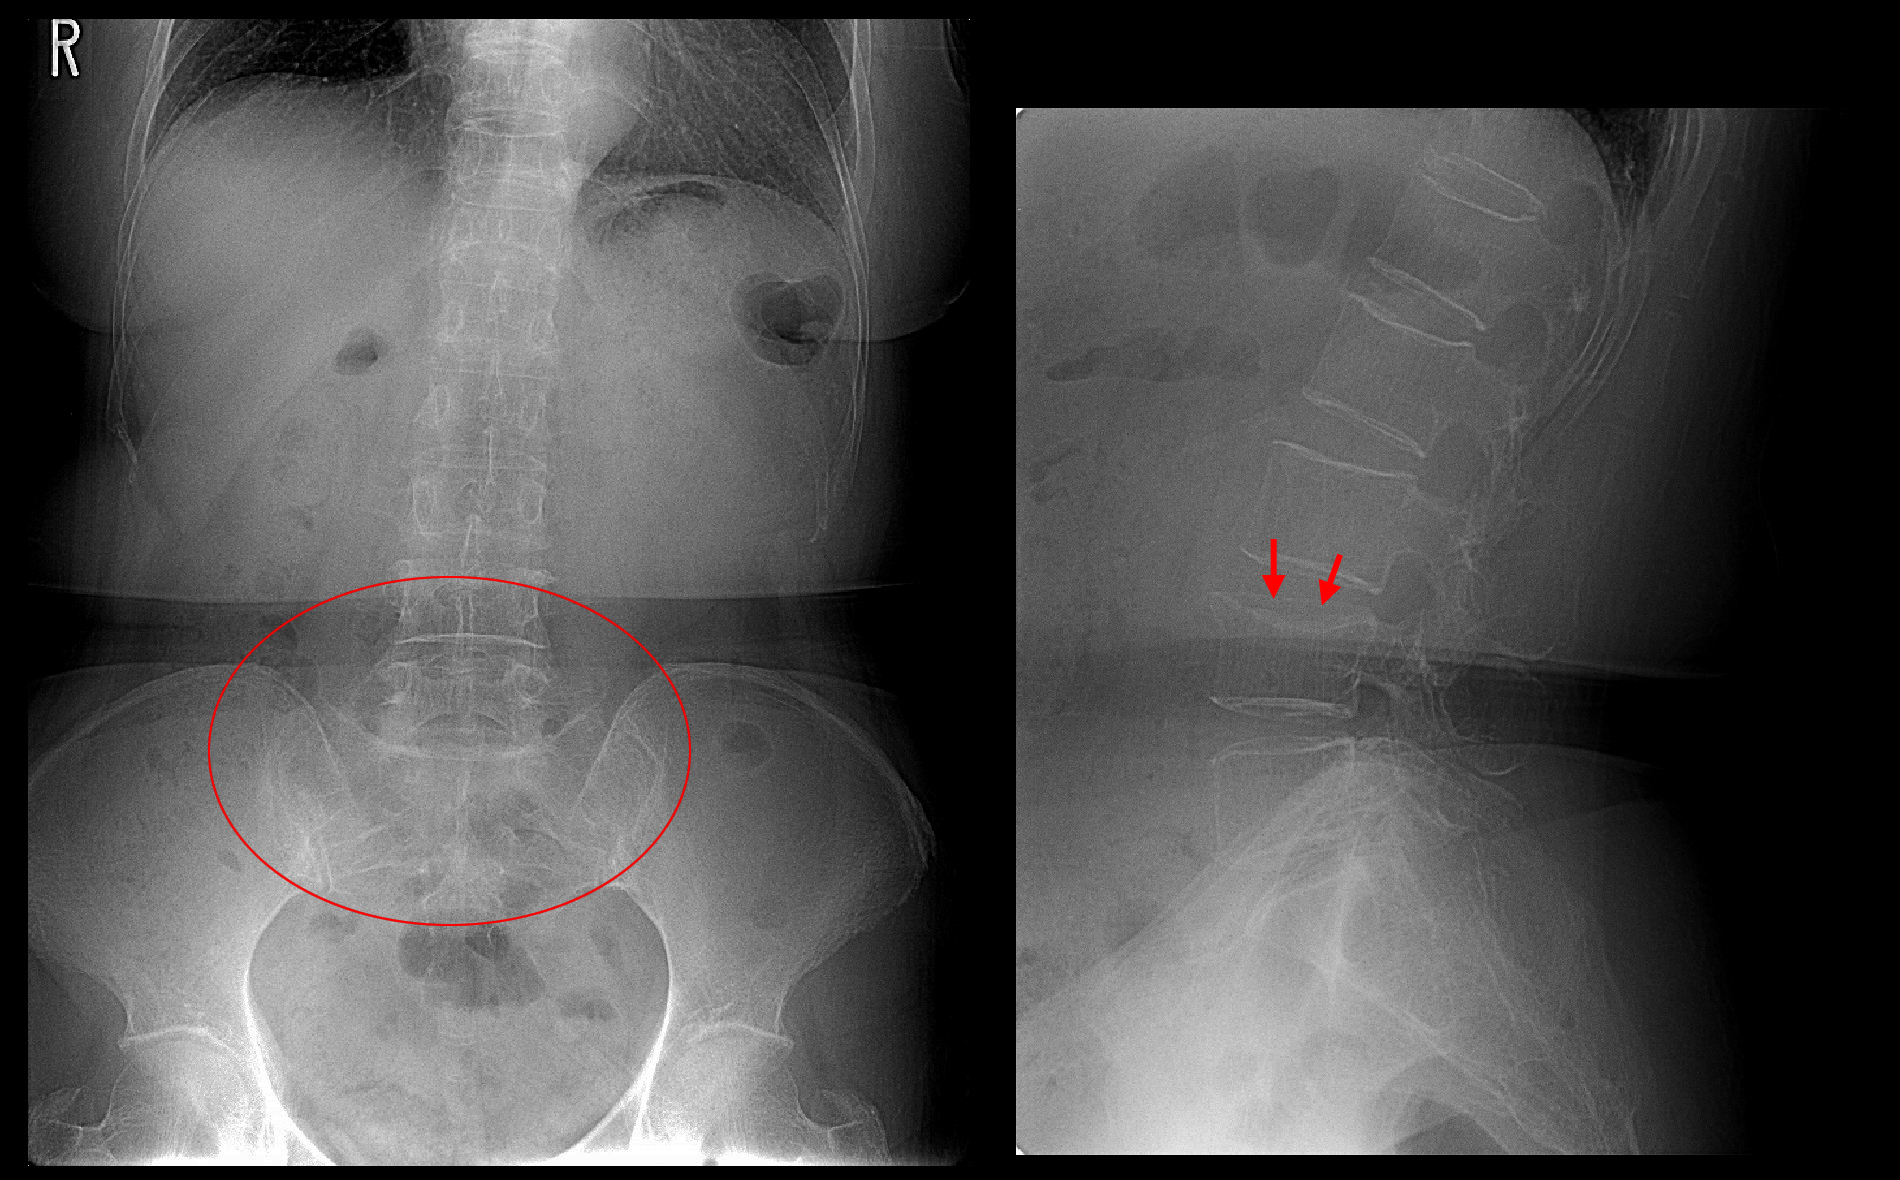

71才女 Xp1.jpg

レントゲン像ではL4(第4腰椎)の上縁が陥凹しています(赤矢印)。後述しますが、骨粗鬆症(こつそしょうしょう)も中等度~重度の印象です。